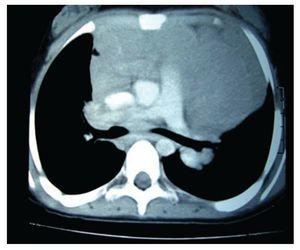

Por estas evidencias, se inició el tratamiento quimioterápico, con ciclos alternos de ciclofosfamida-vincristina-prednisona/doxorrubicinavinblastina-bleomicina-dacarbazina (COP/AVBD). Después del primer ciclo de quimioterapia, desaparecieron los síntomas generales, la adenopatía periférica y hubo disminución de la masa mediastinal; después de tres ciclos de tratamiento se observó persistencia del ensanchamiento mediastinal. Se optó entonces por aplicación de radioterapia en Mantle 25.2 Gy. En el monitoreo radiográfico posterior, se observó que aún perduraba el tumor mediastinal; razón por la que se le administraron dos ciclos más de COP/AVBD. Dado persístela persistencia de la misma imagen, se decidió cambiar el tratamiento a ifosfamida-carboplatino-etopósido (ICE) de tres ciclos. Por estudios radiográficos se observó una masa residual (Imagen 3), por lo que a la paciente se le realizó una toracotomía de exploración; con la que se localiza masa tímica, adherida al pericardio y grandes vasos; se tomó biopsia, que en el análisis histopatológico señaló timofibrolipoma. Por este dato, la decisión a la que llegó fue a la vigilancia de la evolución de la paciente. En la actualidad, su control con placas radiográficas ha revelado que la masa mediastinal permanece sin cambios y sin repercusión clínica evidente.

Imagen 3. Radiografía simple de tórax (de seguimiento) que muestra persistencia de un leve ensanchamiento mediastinal.